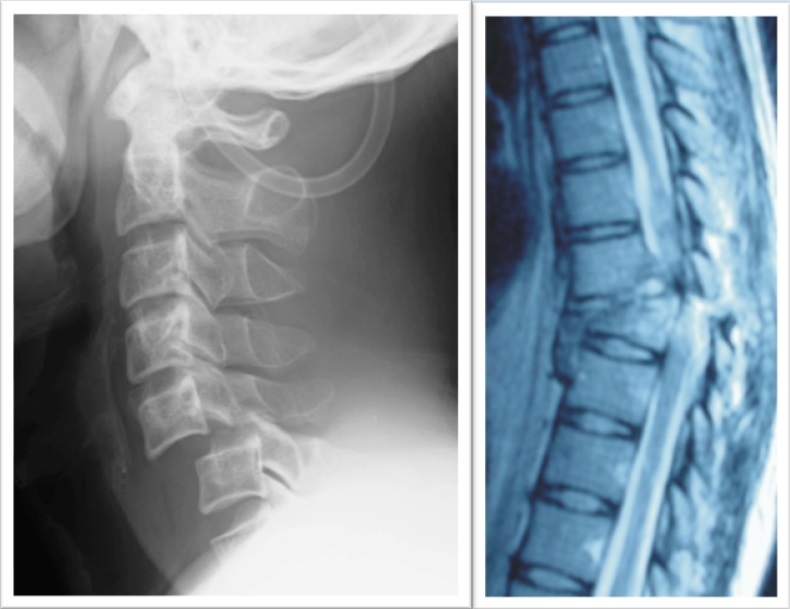

慶應義塾大学医学部教授 岡野栄之さん

「iPS細胞を用いた脊髄損傷の再生医療」